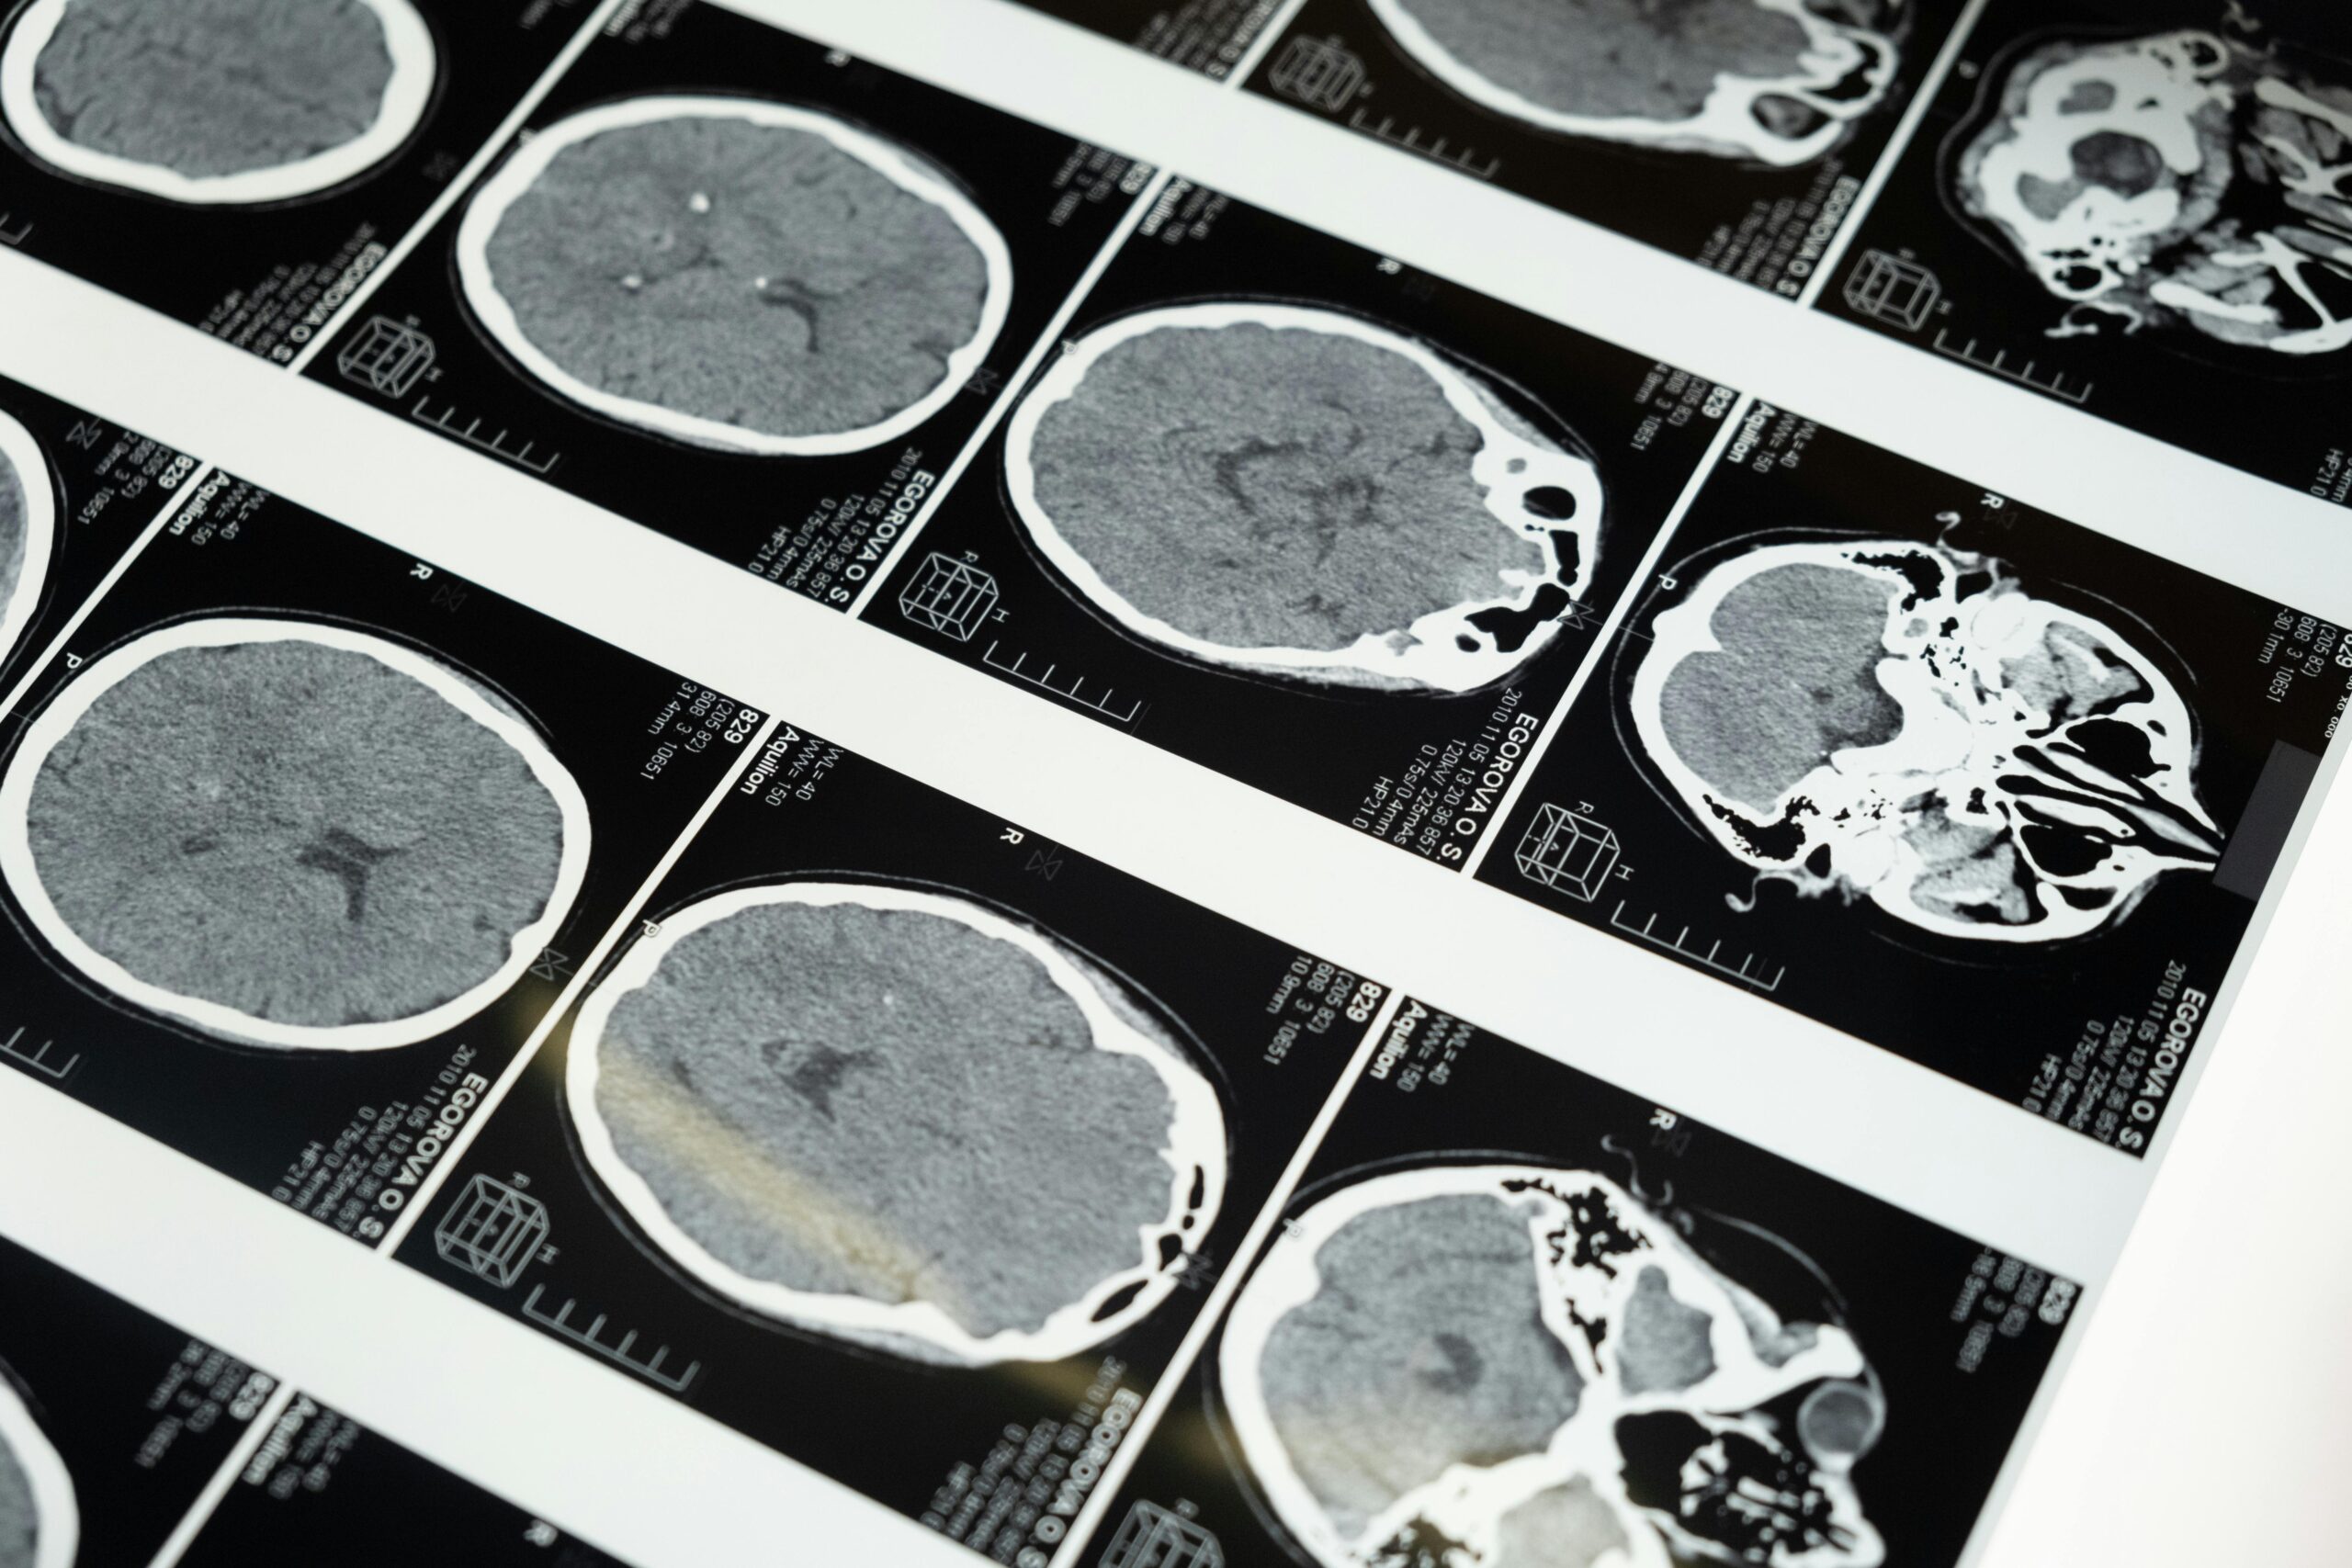

A infecção teve início com sintomas pulmonares e evoluiu até problemas neurológicos, levando médicos a uma biópsia cerebral que resultou na descoberta do parasita.

Durante meses, médicos trataram a paciente para uma pneumonia eosinofílica, já que seus exames de sangue mostravam níveis elevados de eosinófilos, indicadores de infecção parasitária. Contudo, sem sucesso, uma piora nos sintomas neurológicos, como perda de memória, levou a nova investigação.

A remoção do parasita exigiu um procedimento cirúrgico delicado e após a cirurgia, a paciente iniciou tratamento antiparasitário para garantir que não restassem larvas no organismo.